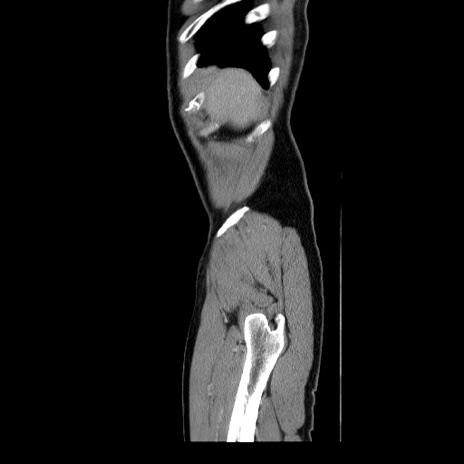

症例34(矢状断像)

【症例】60歳代 男性

【主訴】右鼠径部膨隆

【現病歴】1年程前より右鼠径部膨隆あり。自己にて還納可能だったため放置していた。3時間前より右鼠径部の脱出を認め、還納困難となり受診。

【身体所見】右鼠径部に小児頭大の膨隆あり。弾性硬であり、用手還納は困難。左鼠径部にも膨隆を認める。脱出はなし。